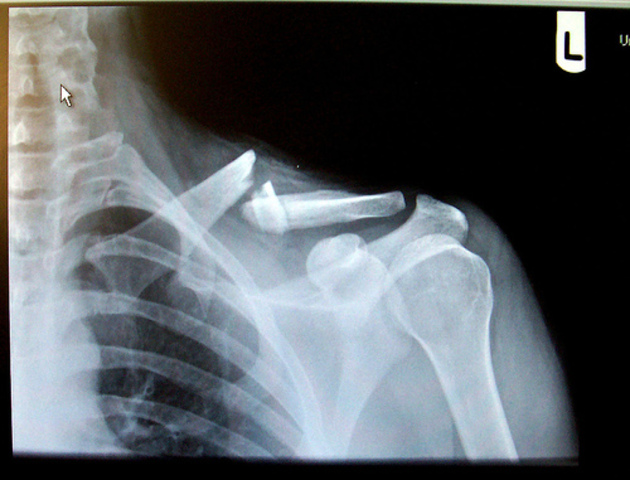

• First Broken Bone

I broke my collar bone nearly in half during baseball practice. It was the first bone I've broken in my entire life.